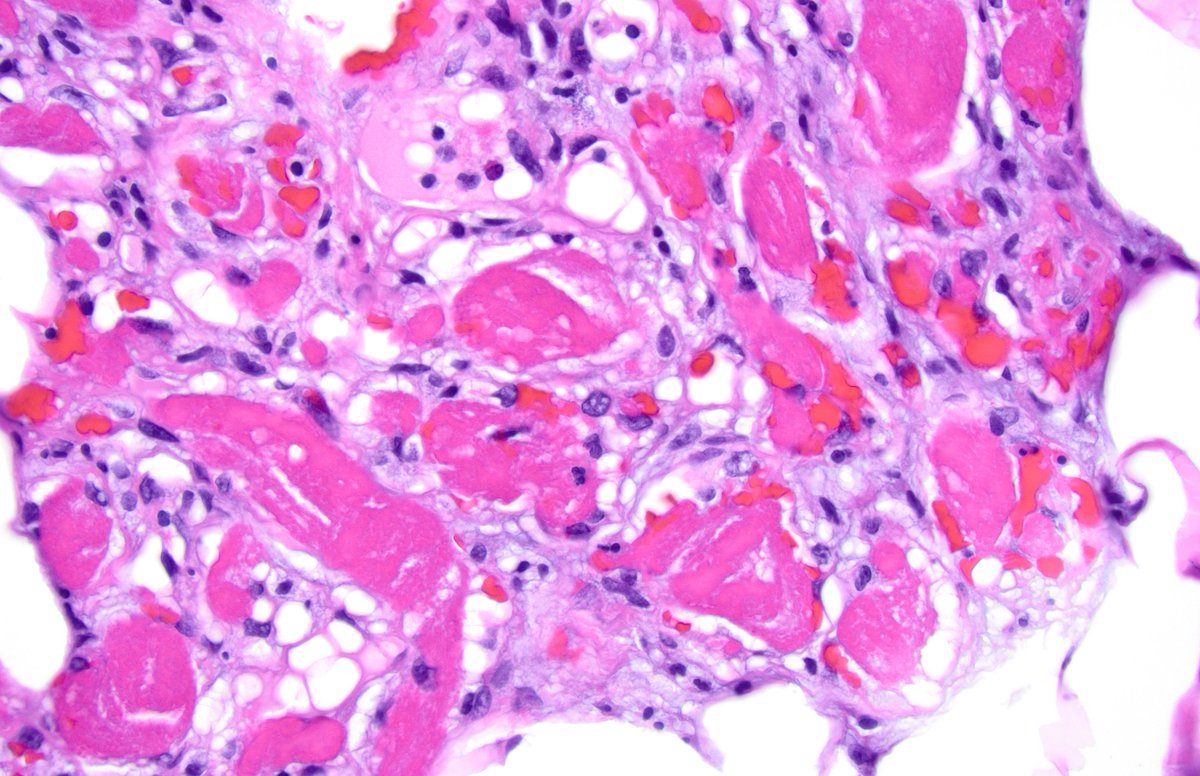

When the thrombi REALLY want to be found! Angiolipoma #bstpath #dermpath